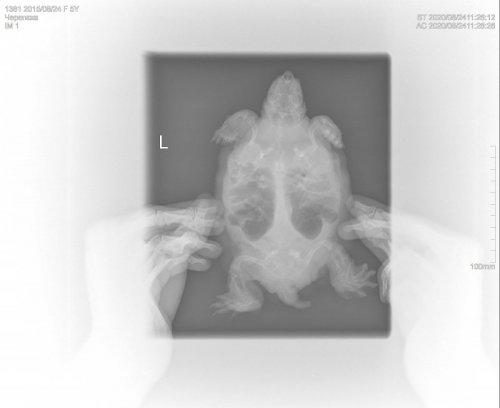

georgiy Ваше имя: Георгий Локация: Россия,г. Набережные челны Опубликовано: 24 августа 2020 Автор Опубликовано: 24 августа 2020 Здравствуйте,сделали рентген.

Консультанты moth Ваше имя: Мария Локация: Москва Опубликовано: 24 августа 2020 Консультанты Опубликовано: 24 августа 2020 @Podolnyi

Podolnyi Ваше имя: Подольный Константин Локация: Украина, Днепр Опубликовано: 25 августа 2020 Опубликовано: 25 августа 2020 У черепахи сильный метеоризм. Для более ясной картины должен быть правый латеральный снимок.